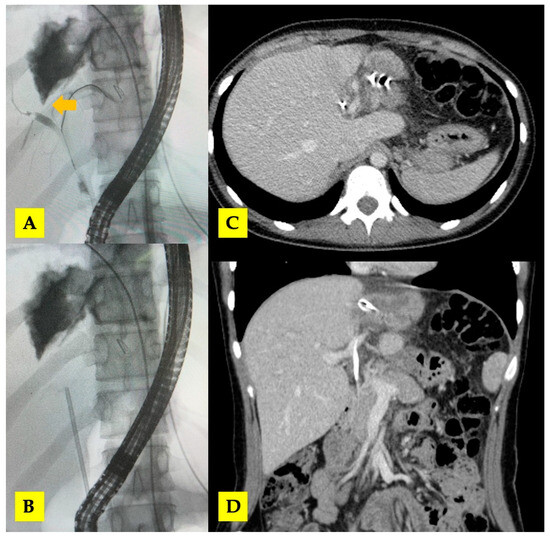

3.1. Case 1

3.2. Case 2